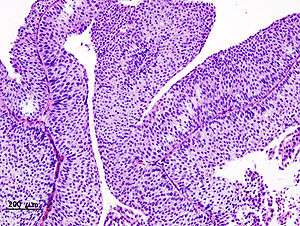

90% of bladder cancers are transitional cell carcinoma. The other 10% are squamous cell carcinoma, adenocarcinoma, sarcoma, small cell carcinoma, and secondary deposits from cancers elsewhere in the body.

Carcinoma in situ (CIS) invariably consists of cytologically high-grade tumour cells.